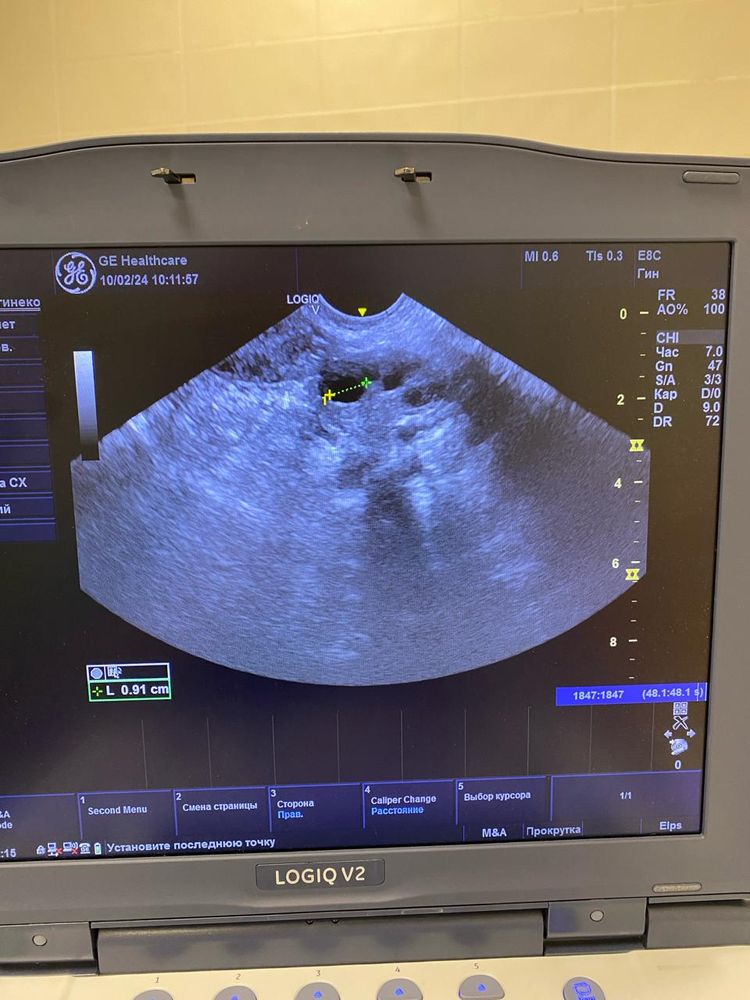

Юлия , Изображение Изображение Изображение Изображение Изображение

Ольга, по этим снимкам овуляция не вот вот. А до нее еще как минимум неделя от этого УЗИ. Фолликулы до 10 мм. И нет доминанта

Ольга, не нужны снимки, нужен протокол УзИ. Описание яичников, срез, ДФ, эндометрий. Врач узи в нескольких проекция смотрит. Я как врач, на этих снимках не вижу ДФ, фолликулы до 10 мм.. Поэтому вообще-то говорить что была овуляция сложно. Сейчас делать УЗИ нет смысла. Ждите менструацию, она начнется со дня на день. Делайте УЗи уже в след цикле в динамике, по мере роста ДФ и подтверждайте овуляцию через 7 дней после ее наступления и берите протоколы УЗИ. Сейчас мы с Вами просто гадаем на кофейной гуще.